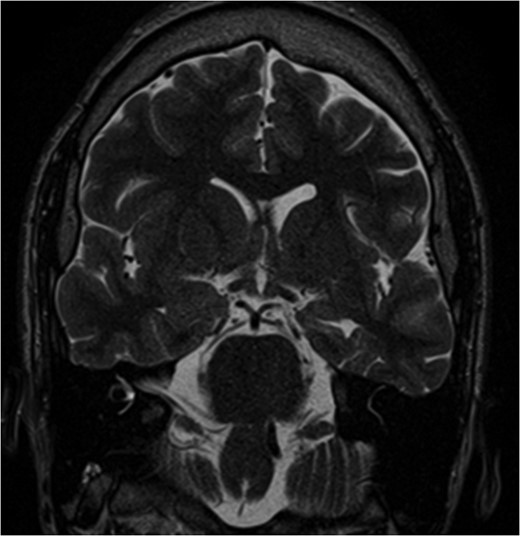

We present a case of a 22-year-old male with history of medically refractory epilepsy since age 7 after suffering from viral encephalitis. He typically has 1–3 seizures per month. Scalp EEG monitoring was able to localize onset to the left temporal lobe and/or left parieto-occipital lobe. Most of the seizures during the study were complex partial with unresponsiveness, orofacial automatisms and right hand twitching. One seizure was atypical, starting with visual changes and appeared to have onset from the left occipital region. MRI was consistent with left mesial temporal sclerosis as well as left parieto-occipital encephalomalacia related to prior encephalitic infarct (Figs 1 and 2). PET scan was pertinent for decreased metabolism in the left mesial temporal lobe. Ictal SPECT was consistent with a left temporal focus. WADA demonstrated left hemispheric language and adequate memory function bilaterally and visual field testing was normal. The patient met criteria for major depressive disorder with psychiatric features on psychiatry evaluation.

Pre-op MRI images. T2 weighted images demonstrate atrophy and hyperintense signal along the left medial temporal lobe.